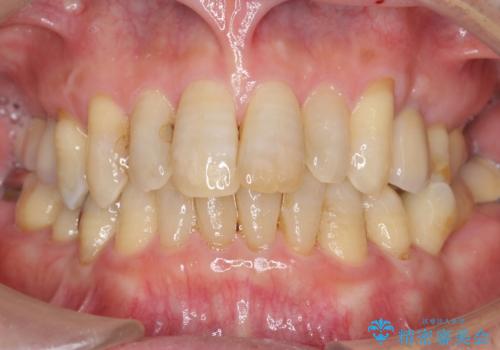

歯科治療や外科手術が苦手な患者様で、治療前はとても怖がっていましたが、インプラント手術後には「思ったよりも大変ではなかった」とおっしゃって下さいました。

元の歯のように咬むことができ、見た目も自然だと喜んで頂けました。

他の部位のインプラント治療もご希望され、現在治療中です。